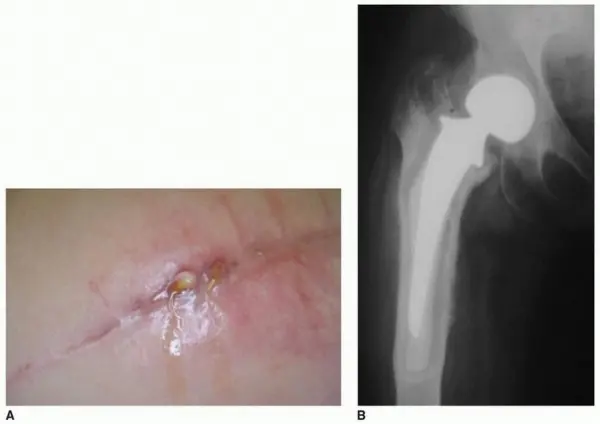

- العدوى الحادة (Acute PJI): تحدث خلال الأسابيع القليلة الأولى بعد الجراحة (عادةً أقل من 3 أشهر). تتميز بأعراض واضحة مثل الألم الشديد، الاحمرار، التورم، خروج القيح من الجرح، والحمى.

- خروج القيح أو السوائل من الجرح: علامة مؤكدة على وجود عدوى، وتظهر عادة في العدوى الحادة.